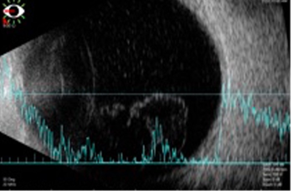

B-scan ultrasonography of the left eye confirmed vitreous opacities without evidence of intraocular, retinal or extraocular mass formation (Figure 1). The optical coherence tomography (OCT) showed isolated pre-retinal adhesions.

Figure 1: B-scan ultrasonography of the left eye with vitreous opacities